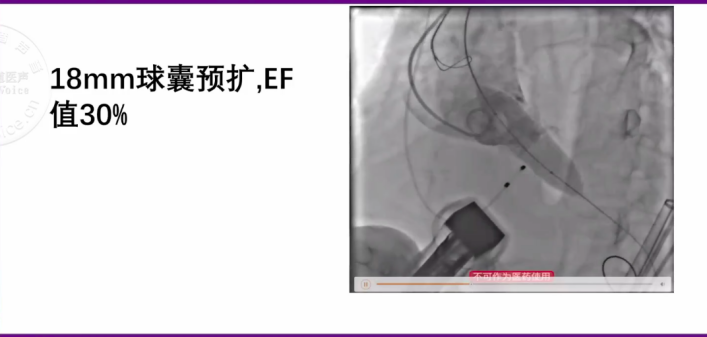

最终,手术团队决定采用静脉镇静的“极简式”麻醉方案,在经胸超声联合DAS指导瓣膜植入。首先采用了12mm外周球囊预扩主动脉瓣口,经胸超声评估,扩张后EF由19%上升至25%,血氧饱和度由93%上升至99%;但初次扩张后患者即刻出现阿斯综合征,经心肺复苏后生命体征回复平稳;随后再次使用18mm球囊预扩,EF进一步上升至30%。在此心功能条件下,决定实施TAVI手术。由于患者入路仅5.4mm,选择植入VitaFlow®一代24mm瓣膜。

图片